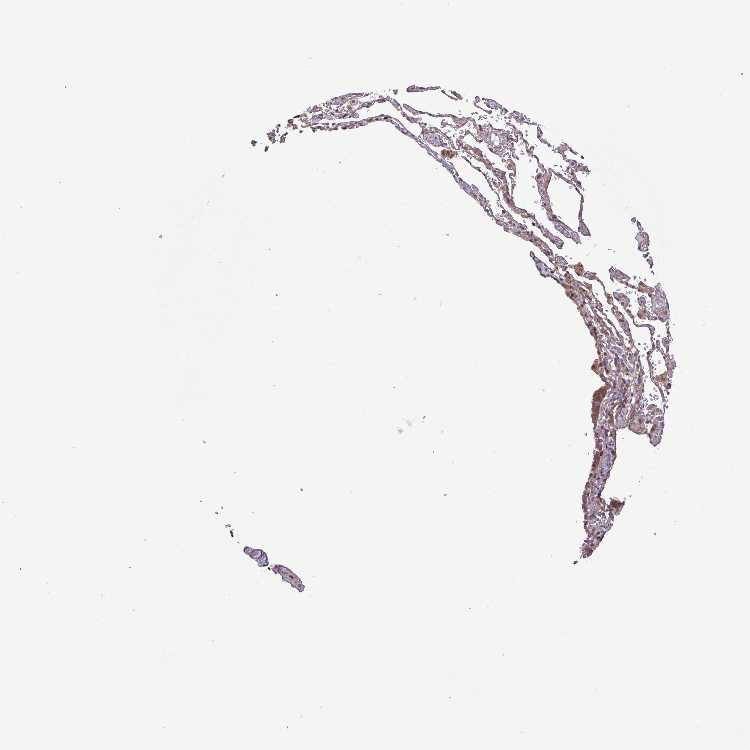

SOFT TISSUE 1 - Antibody stainingi

Antibody staining in the annotated cell types in the current human tissue is reported as not detected, low, medium, or high, based on conventional immunohistochemistry profiling in selected tissues. This score is based on the combination of the staining intensity and fraction of stained cells.

Each image is clickable and will lead to virtual microscopy that enables deeper exploration of all samples and also displays staining intensity scores, fraction scores and subcellular localization as well as patient and tissue information for each sample.

Antibody HPA020468Antibody HPA020480Antibody HPA051583

Chondrocytes Not detectedNot detected-

Fibroblasts LowMediumMedium

SOFT TISSUE 2 - Antibody stainingi

Fibroblasts Not detectedMediumNot detected

Peripheral nerve Not detectedNot detectedNot detected